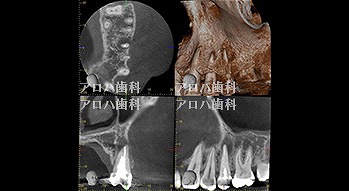

case5

左>頬側よりGP挿入。MB根尖の透過像と一致。P根にも透過像。穿孔を疑う。右>術後1年

左>術前

右>術後1年。

頬側の瘻孔

外科的歯内療法

case8

自費の補綴

頬側に瘻孔

case9

遠心口蓋側に限局性の深いポケット

上顎洞に波及している。

case10

左上に腫脹、圧痛。

根尖部に透過像

術前、術直後、予後

術前、術後